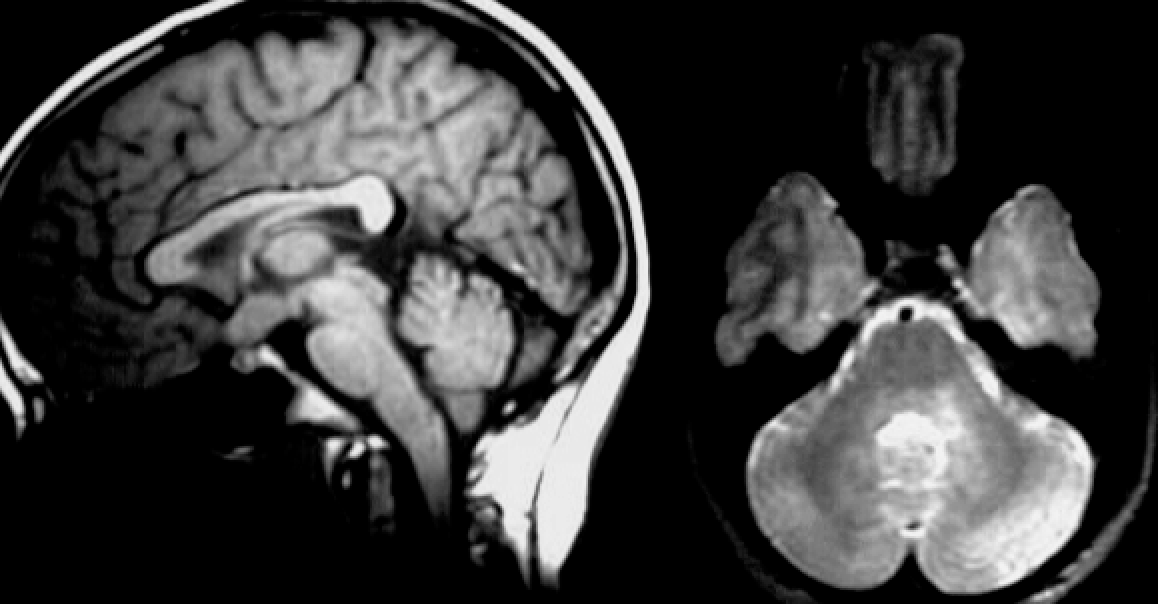

5yo with ataxia, vomiting, and headache

Differential diagnoses and most likely diagnosis?

Differential:

Ependymoma

Juvenile pilocytic astrocytoma

Medulloblastoma.

Most likely:

Ependymoma - 4th ventricle mass, expanding through Magendie and Luschka foramina. Can calcify and have cystic components. Nonhomogeneous contrast enhancement.